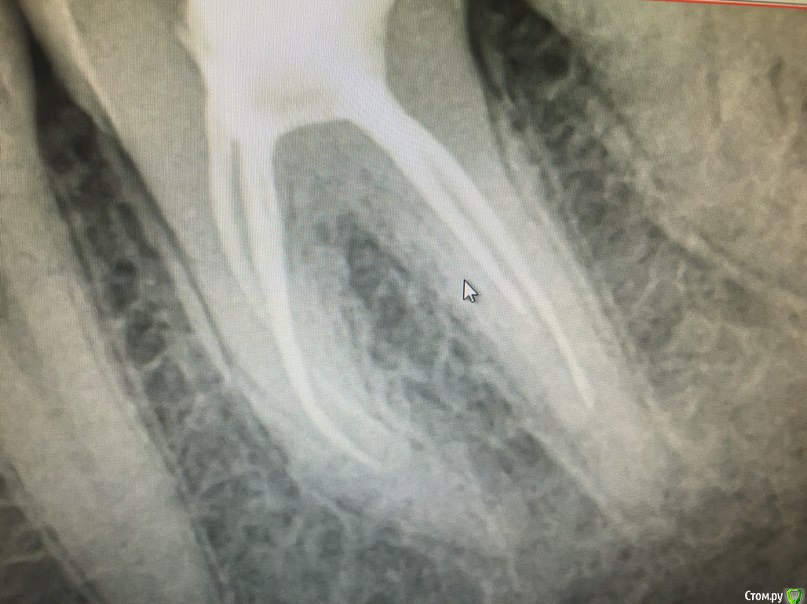

Маргарита03 Опубликовано 11 февраля, 2016 Поделиться Опубликовано 11 февраля, 2016 Добрый вечер всем, нужен совет, нижняя левая 6ка, долго ходила с кариесом многооо лет,решилась пошла к врачу, по советам коллег к врачу высшей категории и 25ти летним стажем, зуб долго сверлили чистили что то делали в каналах и делали много снимков, в итоге поставили временную пломбу и отправили на дней 5 домой, зуб не болел ничего, прихожу через 5 дней врач спрашивает ну как , отвечаю всё хорошо ничего не болело, ну мне ставят пломбу и все, это было 1,5 месяца назад, где-то неделю назад зуб стал реагировать на горячую пищу, я испугалась и побежала в первую повашуюся стоматологию сделать рентген так как та врач что мне лечила его у нее не было времени на неделю вперед,пошла я сделала рентген врач делавший снимок сказал зуб сделан хорошо но каналы до конца не пройдены!Чем это чревато я знаю не по наслышке, я так потеряла 6ку справа и лечу сейчас воспаление 7ки справа по той же причине, так вот пришла я сегодня к врачу которая лечила мне этот зуб и говорю так и так врач который снимок делал сказал срочно перелечивать и пройти все каналы пока не началось воспаление показываю ей снимок она говорит а мы дальше и не сможем пролезть в каналы,это максимум, я в шоке, один врач говорит надо обязательно второй врач говорит нет не надо.в итоге сегодня нашли мне дыру в соседнем зубе в 7ке как оказалось не маленькую залечили врач сказала что скорее всего он и реагировал, так вот вопрос права ли она что можно так оставить мой зуб? прикрепляю фото снимка этой 6ки. Ссылка на комментарий

Zlata-doctor Опубликовано 12 февраля, 2016 Поделиться Опубликовано 12 февраля, 2016 маловероятно, что на холод давал реакцию этот зуб.Я бы пока не лезла туда, сделайте повторный снимок через год, если ничего не будет беспокоить.Через год сравните динамику (стоматолог, ессно, это должен делать). Картинка не идеальная, конечно, но и не совсем прям плохая. Мы не знаем что и как там было. При нормальной коронковой герметичности прогноз благоприятный. Не надо быть " в шоке" и " срочно перелечивать" тоже не надо кидаться. 1 Ссылка на комментарий

Ker Опубликовано 12 февраля, 2016 Поделиться Опубликовано 12 февраля, 2016 (изменено) маловероятно, что на холод давал реакцию этот зуб.Я бы пока не лезла туда, сделайте повторный снимок через год, если ничего не будет беспокоить.Через год сравните динамику (стоматолог, ессно, это должен делать). Картинка не идеальная, конечно, но и не совсем прям плохая. Мы не знаем что и как там было. При нормальной коронковой герметичности прогноз благоприятный. Не надо быть " в шоке" и " срочно перелечивать" тоже не надо кидаться.Периодонтальная щель стерлась на обоих верхушках. Полагаю что развития чего либо нехорошего стоит ждать, особенно в долгосрочной перспективе.Я бы залез, тем более что зуб не выглядит сложным, Изменено 12 февраля, 2016 пользователем Ker Ссылка на комментарий